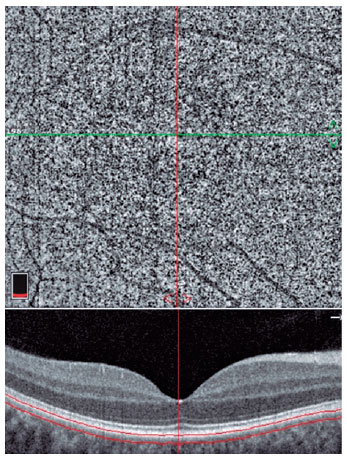

Ninety-eight eyes of patients were compared to those of healthy controls. Patients who presented to the internal disease clinic for routine health control and whose vitamin S level was ≤20 ng/mL were enrolled in the study group. Individuals whose serum vitamin D levels were ≥30 ng/mL were allocated to the control group. Patients with retinal vascular diseases (i.e., any stage of diabetic and hypertensive retinopathy, senile maculopathy, and uveitis); any kind of nystagmus; a history of previous ocular surgery, amblyopia, glaucoma, or systemic diseases (i.e., diabetes, arterial hypertension, dyslipidemia, vasculitis, and rheumatologic and neurologic diseases); optic nerve disease; spherical power >3 diopters (D); cylindrical power >1.5 D; axial length (AL) >26 mm and <20 mm; and best-corrected visual acuity (BCVA) <1.00 decimal were excluded. In both groups, one eye that was eligible for inclusion was randomly selected. Patients whose body mass index was <18 kg/m2 and >25 kg/m2 and who were taking vitamin D analogs were also excluded. Images with artifacts and signal strength index <60 were not used. All patients provided informed consent. After a complete examination, macula-centered photos were automatically taken by a single expert who was blinded to the study using RTVue-XR Avanti (Optovue, Inc., CA, USA) on a 6.0 × 6.0-mm scan size. The vessel density (VD) in the superficial (SCP) and deep capillary plexus (DCP), choriocapillaris flow area, and foveal avascular zone (FAZ) area were measured (Figures 1, 2, 3, 4). OCT-A examinations and data were analyzed by an author who was blinded to the study groups. The OCT-A parameters were automatically calculated using the software embedded in the devices. The retinal microvasculature was analyzed using the automated retinal layer segmentation algorithm available on the device. In cases with insufficient automatic layer segmentation, the correction was manually performed.

To our knowledge, no study has investigated the early effects of vitamin D deficiency on retinal microvascularity using OCT-A. In this case-control study, we enrolled patients who did not have any other eye or systemic diseases. We observed significantly increased VD in the whole image, parafoveal, and perifoveal regions of the DCP in our study group. Additionally, we observed a negative correlation between the serum vitamin D levels and VD in the whole image and the parafoveal and perifoveal regions of the DCP.

This study was not designed to determine causality. Nevertheless, we thought that increased VD, especially in DCP, might result from early-stage, vitamin D deficiency-associated retinal microvascular damage and reversible proliferation of pericytes and vascular smooth muscle as well as endothelial cells. The increase in VD does not indicate neovascularization because we did not detect any sign of neovascularization on fundus examination and colored fundus photography of the participants. Moreover, we believed that DCP was most affected owing to the prominent expression of D-dependent Ca+2-binding protein and VDR in the retina’s outer plexiform layer, as mentioned above. The negative correlation could indicate that vitamin D deficiency-associated retinal vasculopathy worsens as the serum vitamin D level decreases.